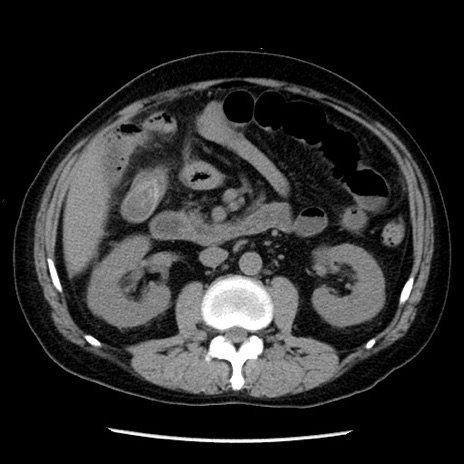

症例29(横断像)

【症例】40歳代男性

【現病歴】2日前から胃痛あり。徐々に周期的な激痛に変化した。本日になっても激痛があるため受診。

【身体所見】意識清明、BT 38-39℃台あり、腹部:膨満、やや硬、右下腹部に圧痛あり。

【データ】WBC 8500、CRP 23.26